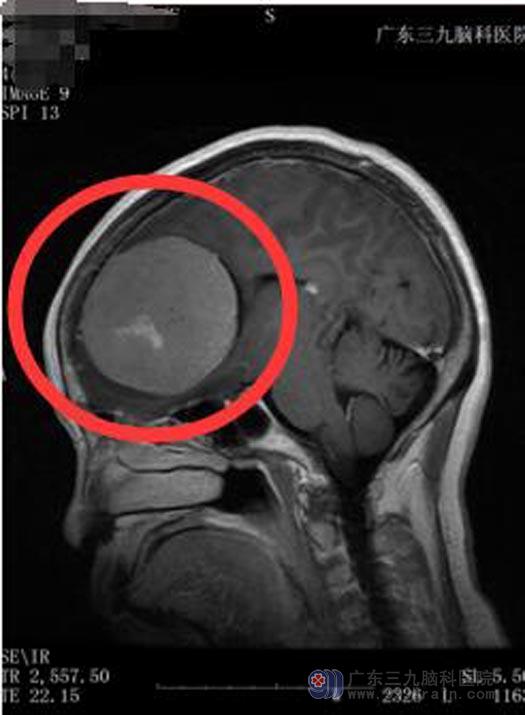

在广州工作的两个儿子将母亲接到广东三九脑科医院,MR检查结果示:左额部廉旁占位性病变,考虑脑膜瘤可能性大,范围约70.2mm×69.8mm×64.8mm。